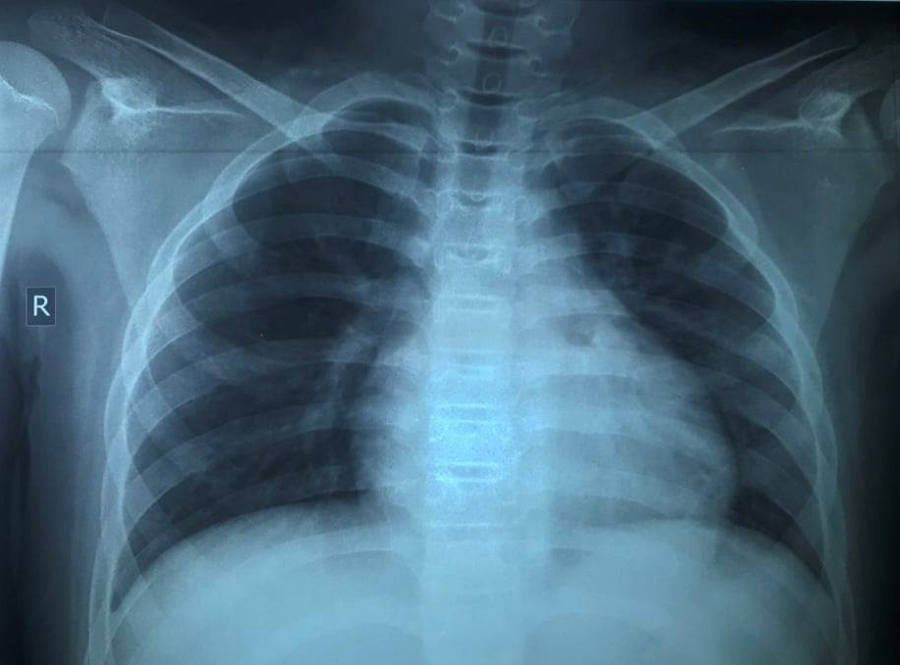

| Hình ảnh X-quang phối của trẻ lúc nhập viện, tổn thương phổi nặng, dù triệu chứng rất kín đáo. Ảnh: BSCC. |

Tại bệnh viện, nhịp thở của bệnh nhi 26-28 lần/phút, không quá nhanh so với tuổi. Tuy nhiên, chỉ số SpO2 của trẻ giảm xuống 92%, kết quả xét nghiệm PCR dương tính với nCoV. Kết quả chụp X-quang có tổn thương phổi nhiều, rối loạn đông máu.